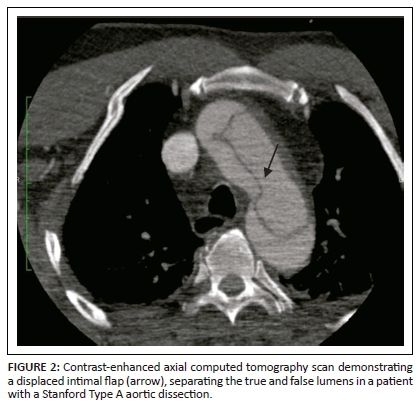

On unenhanced CT, intraluminal displacement of intimal calcifications can occasionally be seen, suggesting AD (Figure 1). A linear hypodense internally displaced structure representing the intimo-medial flap, separating the true and false lumens, is the most important CT finding seen in approximately 70% of cases (Figures 2, 5 and 8c).7 In the present era of endovascular management, differentiation of the true and false lumen is important in planning the management. The true lumen directly communicates with the aorta, and intimal calcifications, if present, surround it (Figure 3a). The calibre of the true lumen is smaller as compared to false lumen, which wedges around it owing to permanent systolic pressure. Fine linear scattered hypodense areas within the false lumen are termed the Cobweb sign (Figure 3a). It is specific for the false lumen and represents collagenous residual media fibres.8 The beak sign is another useful sign for the false lumen which represents a wedge of haematoma at the distal end of the false lumen on cross-sectional imaging (Figure 3b). It forms an acute angle between the dissection flap and vessel wall and represents the site of propagation.9 The false lumen shows less contrast enhancement compared to the true lumen in the early arterial phase and may appear hyperdense to the true lumen in the venous phase owing to contrast pooling (Figure 4).